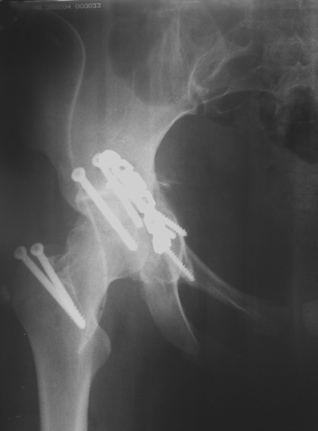

30/11/04 |  30/11/04 |  30/11/04 |  14/12/04 |  14/12/04 |  14/02/05 |  14/02/05 |  21/02/05 | Уважаемые коллеги! Случилось вторичное смещение вертлужной впадины после операции. Посоветуйте, что делать. Пациентка 18 лет. Травма 19.11.04. D.s.: Закрытыый Т-образный высокий перелом правой вертлужной впадины. Закрытый перелом м\мыщелкового возвышения левой б\берцовой кости. 9.12.04 операция - открытая репозиция, остеосинтез переломам вертлужной впадины. 30.12.05 выписаны на амбулаторное лечение с рекомендациями не вставать на правую ногу. 14.02.05 при контрольном осмотре на Р-граммах выявлено вторичное смещение передней колонны. Клинически подвывиха нет, имеется умеренная приводящая контрактура правого тазобедренного сустава, гипотрофия мышц н\конечностей. Госпитализирована в травмотделение. Выполнено КТ. Имеется смещение передней колонны кнутриЮ диастаз 8 мм. Посоветуйте пожалуйста, что предпринять в данной ситуации.

У больной имеется диастаз лонных и седалищных костей, то есть "разорвано" тазовое кольцо. В перспективе возможно образование ложного сустава на уровне основания лонной кости с болевым синдромом, поскольку седалищная кость не срастется.

2. ограничить двигательную активность до 6 мес. (не нагружать ногу, носить тазовый корсет-пояс и т.д.) с контролем сращения. Вроде бы на Р-граммах угадывается слабая тень формирующегося костного мостика по l. iliopectinea, это место в представленные срезы КТ не попало. Если к 6 мес. ничего не нарастет, то см. пункт 1.

В любом случае начинать нагрузку на эту ногу до уверенности в сращении - большая вероятность исхода в псевдартроз с болевым синдромом.